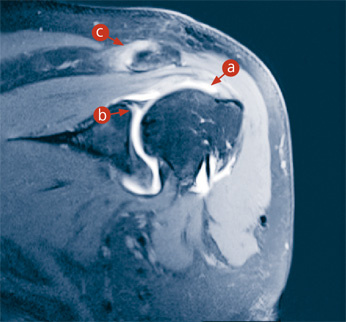

Abb. 2a

CT-Darstellung einer Lebermetastase (Tochtergeschwulst eines Dickdarmtumors – grauer Fleck innerhalb des roten Kreises).